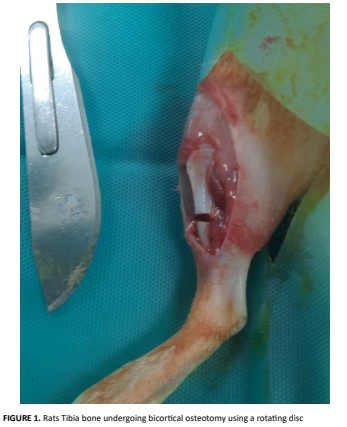

Medicina Veterinaria